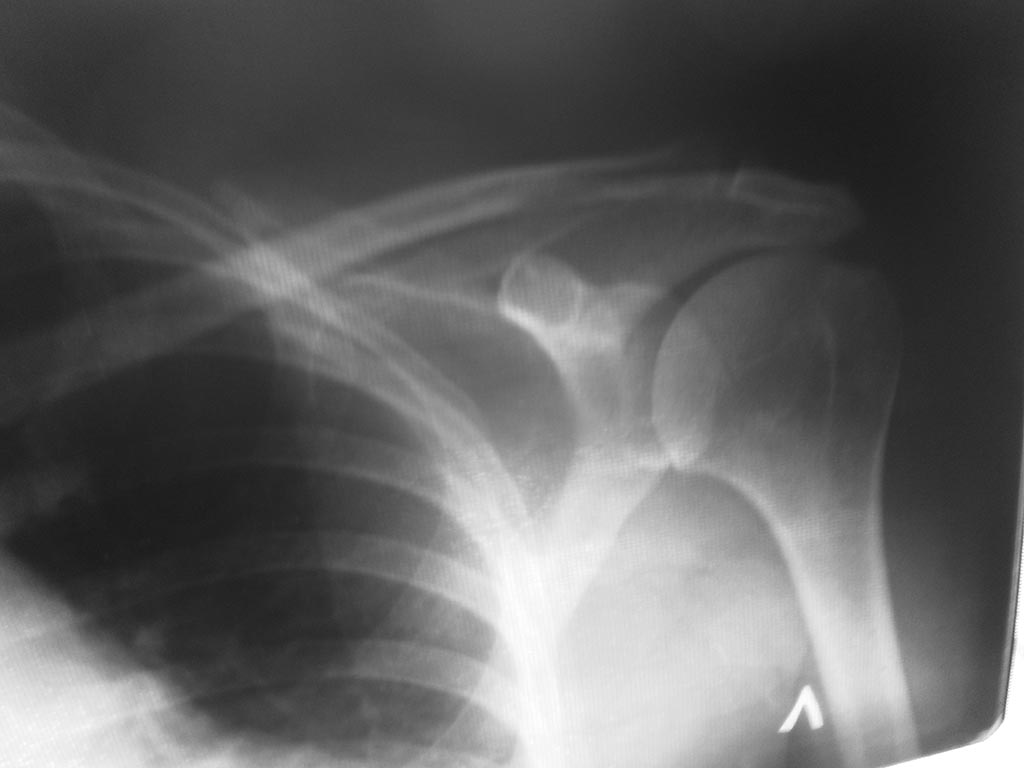

Мне 57 лет получила травму 5 месяцев назад -упала на согнутую руку в локте. Беспокоят боли . особенно в ночное время.невозможно отвести руку, поднять, завести за спину.R- снимок левого плечевого сустава

Описание сделает врач-рентгенолог. Однако помощь в этой ситуации вряд ли исчерпывается описанием снимка. На снимке проблем не видно, но снимок показывает только костные структуры.

Рентгенограмма без признаков костной патологии. Если позволите догадаться, Вы бы хотели избавиться от болей в левом плечевом суставе.

Описанные симптомы подходят к повреждению сухожилий вращающей манжеты плечевого сустава. Для подтверждения этого диагноза требуется сделать либо УЗИ, либо МРТ, поскольку мягкие ткани на рентгене оценить можно иногда, и лишь косвенно, а в вашем случае невозможно.